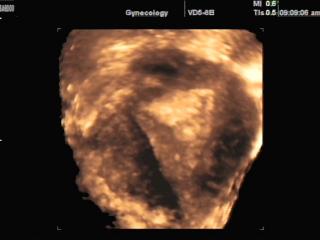

Ectopic pregnancy, 3D

SonoAce-8000. Ectopic pregnancy, 3D.